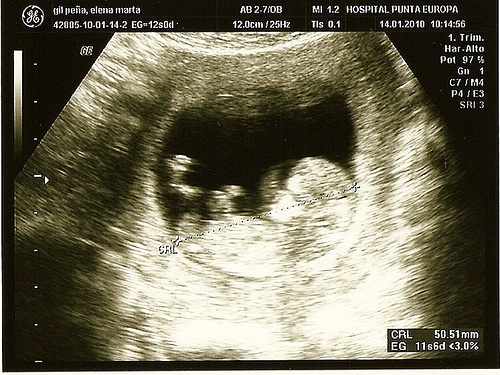

Ecografia o ultrasuoni

Serve sia per individuare dei problemi, sia per ottenere le prime immagini del vostro bambino. Questa tecnica aiuta a scoprire il sesso del bambino, ma anche a identificare le prime anomalie visibili, come difetti del cuore o alterazioni dei cromosomi.

Le ecografie di secondo livello, invece, sono un esame consigliato per osservare da vicino possibili difetti del feto. Si consigliano quando, negli esami di routine, è stata identificata un’anomalia. La tecnica non è invasiva: un apparecchio produce un’immagine grazie a ultrasuoni che, senza nuocere al bambino, permette di osservare l’ambiente interno dell’utero.